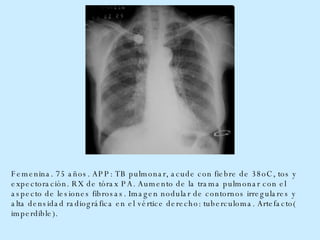

Femenina. 75 años. APP: TB pulmonar, acude con fiebre de 38oC, tos y expectoración. RX de tórax PA. Aumento de la trama pulmonar con el aspecto de lesiones fibrosas. Imagen nodular de contornos irregulares y alta densidad radiográfica en el vértice derecho: tuberculoma. Artefacto( imperdible).

Femenina. 75 años.APP: TB pulmonar, acude con fiebre de 38oC, tos y expectoración. RX de tórax PA. Aumento de la trama pulmonar con el aspecto de lesiones fibrosas. Imagen nodular de contornos irregulares y alta densidad radiográfica en el vértice derecho: tuberculoma. Artefacto( imperdible).